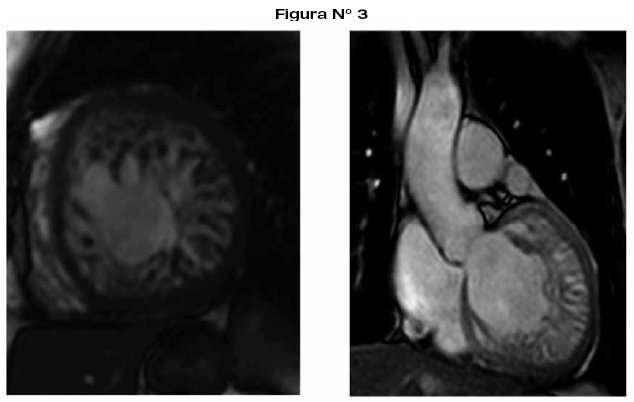

La resonancia nuclear magnética es el mejor método para evaluar el volumen del ventrículo derecho, evalúa con precisión el tamaño, la masa, la morfología, y la función, así como flujos valvulares, calculando con el débito, los cortocircuitos y la regurgitación24,25,33